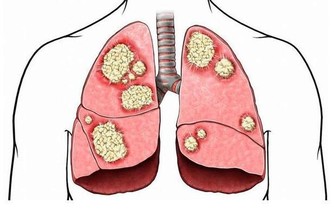

事實上,包括胃癌、宮頸癌、肝癌、肺癌等,常在晚期被發現。為什麼會發生這些?

此外,更可怕的是,許多類型的癌症正在迅速發展,並可以在短短幾個月內發展到晚期,擴散和轉移。